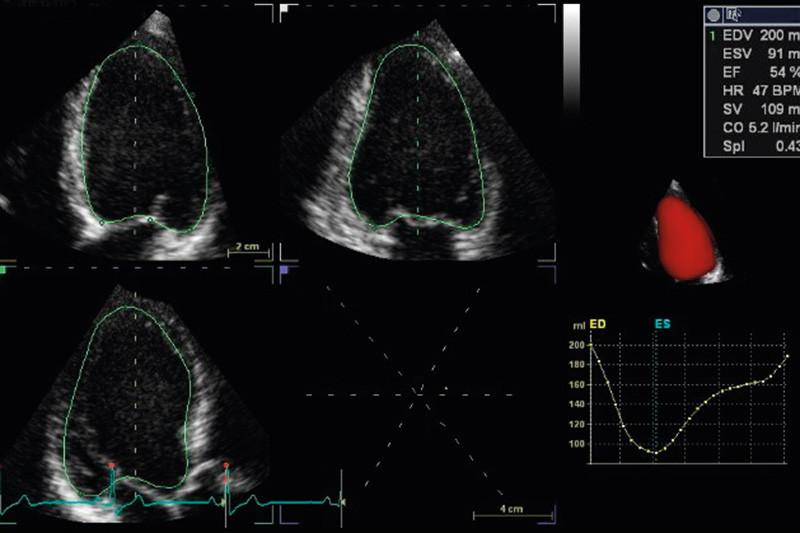

Automatic volume analysis indicating the left ventricular ejection fraction (EF) can be performed from three orthogonal planes (4) or from the full volume cardiac dataset, with representation of the volume curve in the entire cardiac cycle (Figure 1). Theoretically, 3D echocardiography has an advantage in that the volume is not calculated from a geometric model, but can be estimated directly from a full volume recording. This also avoids cutting through the apex so that the volume is artificially low, which is frequently the case with conventional two-dimensional imaging. The method has been validated against cardiac MRI scans, with good agreement obtained for left ventricular volumes and ejection fraction (2, 4) – (7).

Figure 1  Representation of the volume curve in the entire cardiac cycle (bottom right in image). Volume data and ejection…

Figure 1 Representation of the volume curve in the entire cardiac cycle (bottom right in image). Volume data and ejection fraction (EF) are indicated. The figure also shows the three standard planes from the full volume recording.